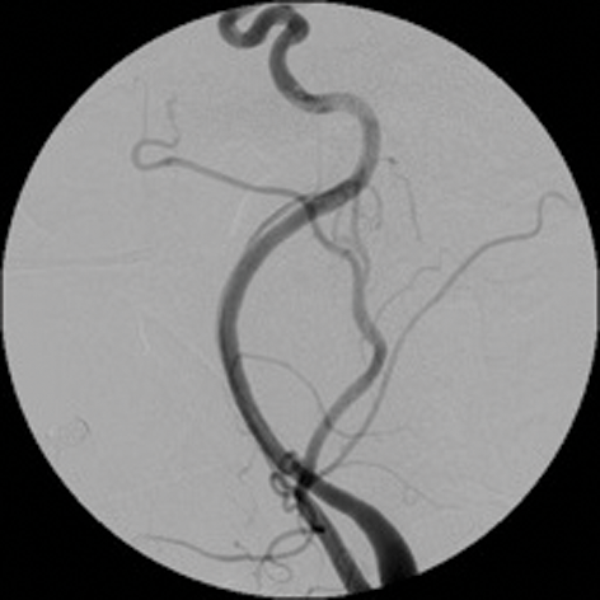

Arterio-venous (AV) fistulae are abnormal connections between arteries and veins which can be congenital, spontaneous or traumatic. Treatment of AV fistulae of head and neck also falls within the remit of interventional neuroradiology. These lesions are often difficult to treat surgically because of multiplicity of feeders and difficulty in access etc.

Endovascular treatment of AV fistulas involves preservation of the normal vasculature and occluding both the distal and proximal vessels of the fistula.

Detachable balloons, particles and / or sclerosants, and stents are used in the endovascular treatment of these lesions. (Figure 3 shows a case of a traumatic external carotid-jugular AV fistula treated by coil embolisation).

Figure 3: ECA- jugular fistula before and after embolisation.